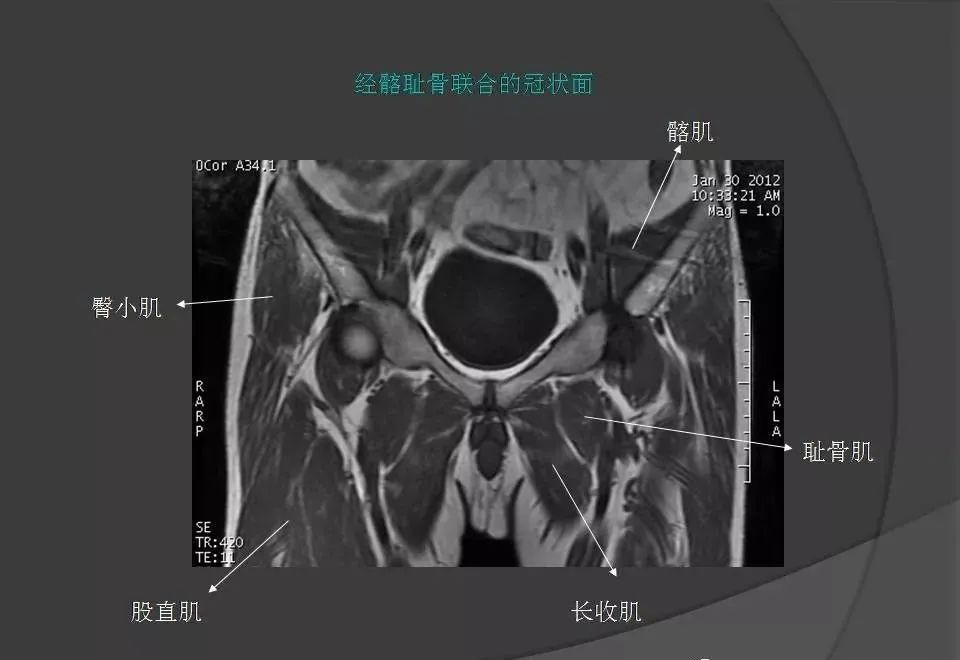

女性盆腔ct连续断层解剖图,盆腔mri影像病例分析